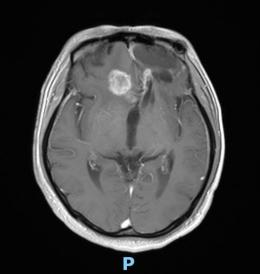

44歲的郭先生(化姓)為膠質(zhì)瘤復(fù)發(fā)患者,復(fù)查發(fā)現(xiàn)顱內(nèi)占位進(jìn)行性進(jìn)展1周,MRI檢查提示瘤體已累積到胼胝體,且瘤體位置較深,手術(shù)難度極高。面對(duì)這一挑戰(zhàn),王虎教授團(tuán)隊(duì)決定采用多種先進(jìn)技術(shù)輔助手術(shù),其中最為引人注目的就是首次引入的細(xì)胞級(jí)顯微鏡EndoSCell?。該設(shè)備是目前全球唯一實(shí)時(shí)在體細(xì)胞級(jí)顯影的儀器,可以輔助醫(yī)生從細(xì)胞層面區(qū)分腫瘤組織與正常組織,從而做到細(xì)胞級(jí)精準(zhǔn)切除。

患者術(shù)前核磁影像